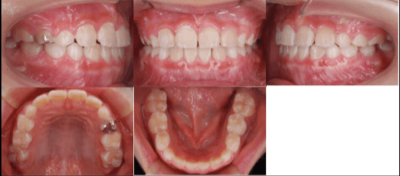

<治療後>

初診時は7歳2ヶ月で、前歯のかみ合わせが反対になっていることが主訴で来院されました。前歯部の反対咬合の診断により、「インビザライン・ファースト」を使用して治療を開始しました。

治療期間は6ヶ月で、下顎の前歯が上顎の前歯より前に出ている「交叉咬合」が改善されました。

治療のリスクとしては、矯正治療時に歯が移動する際に生じる痛み、歯根の吸収、むし歯が挙げられます。治療費用はおよそ40万円です。